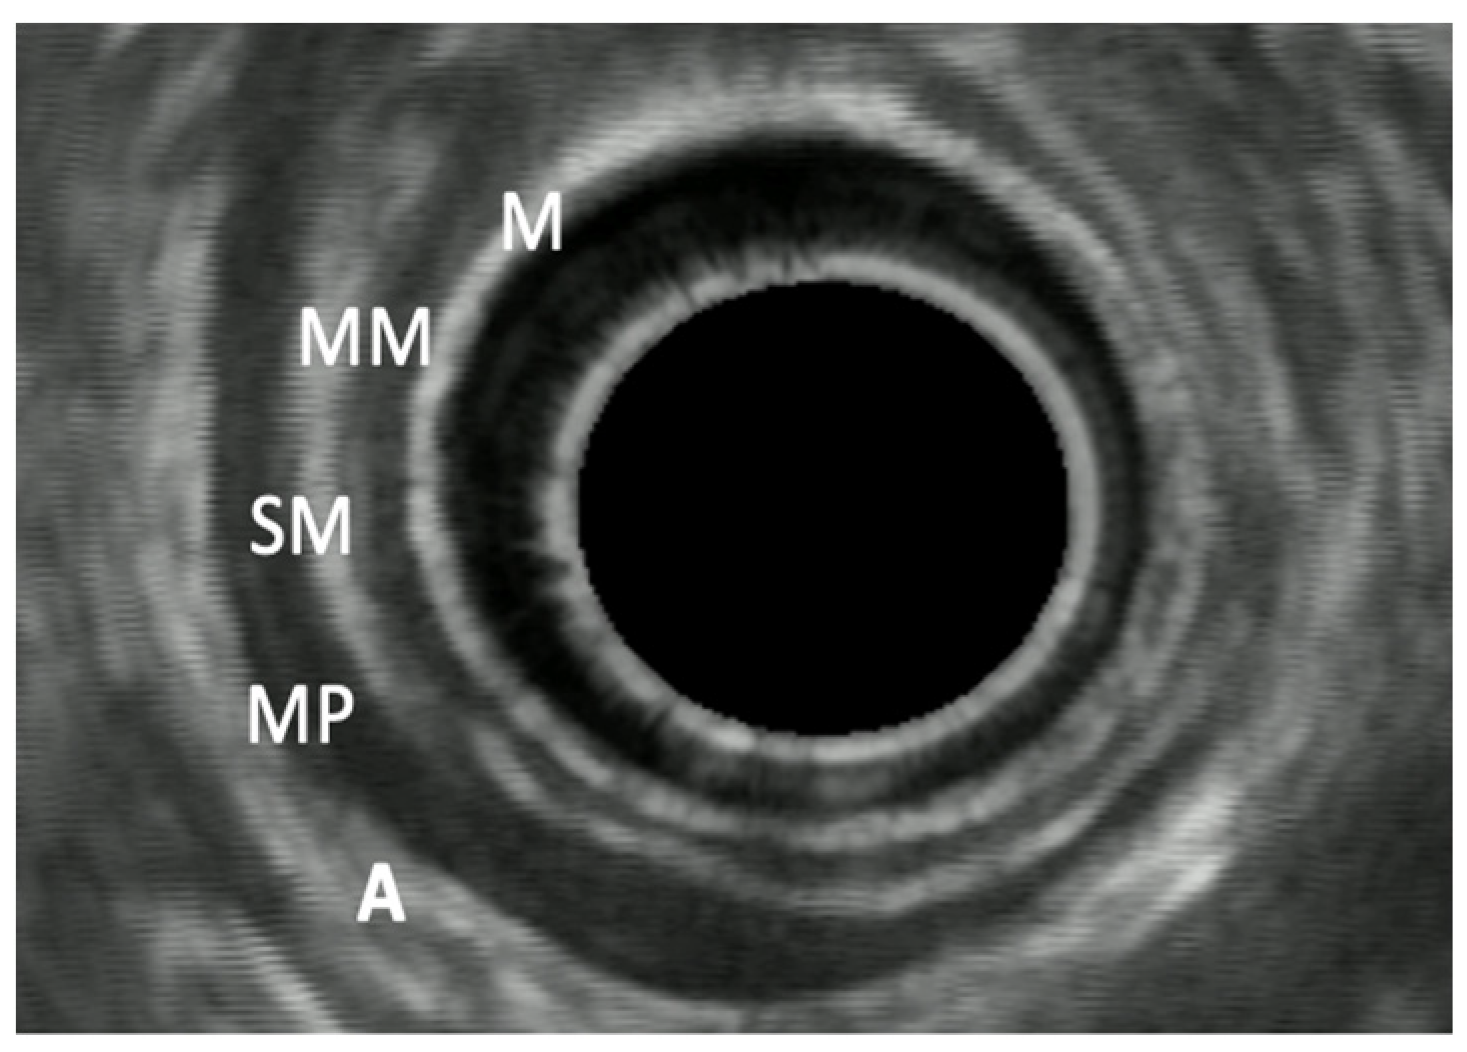

7. Endoscopic Rectal Ultrasound

8. Rectal Neoplastic Lesions

8.1. Rectal Superficial Cancer

8.2. Advanced Rectal Cancer